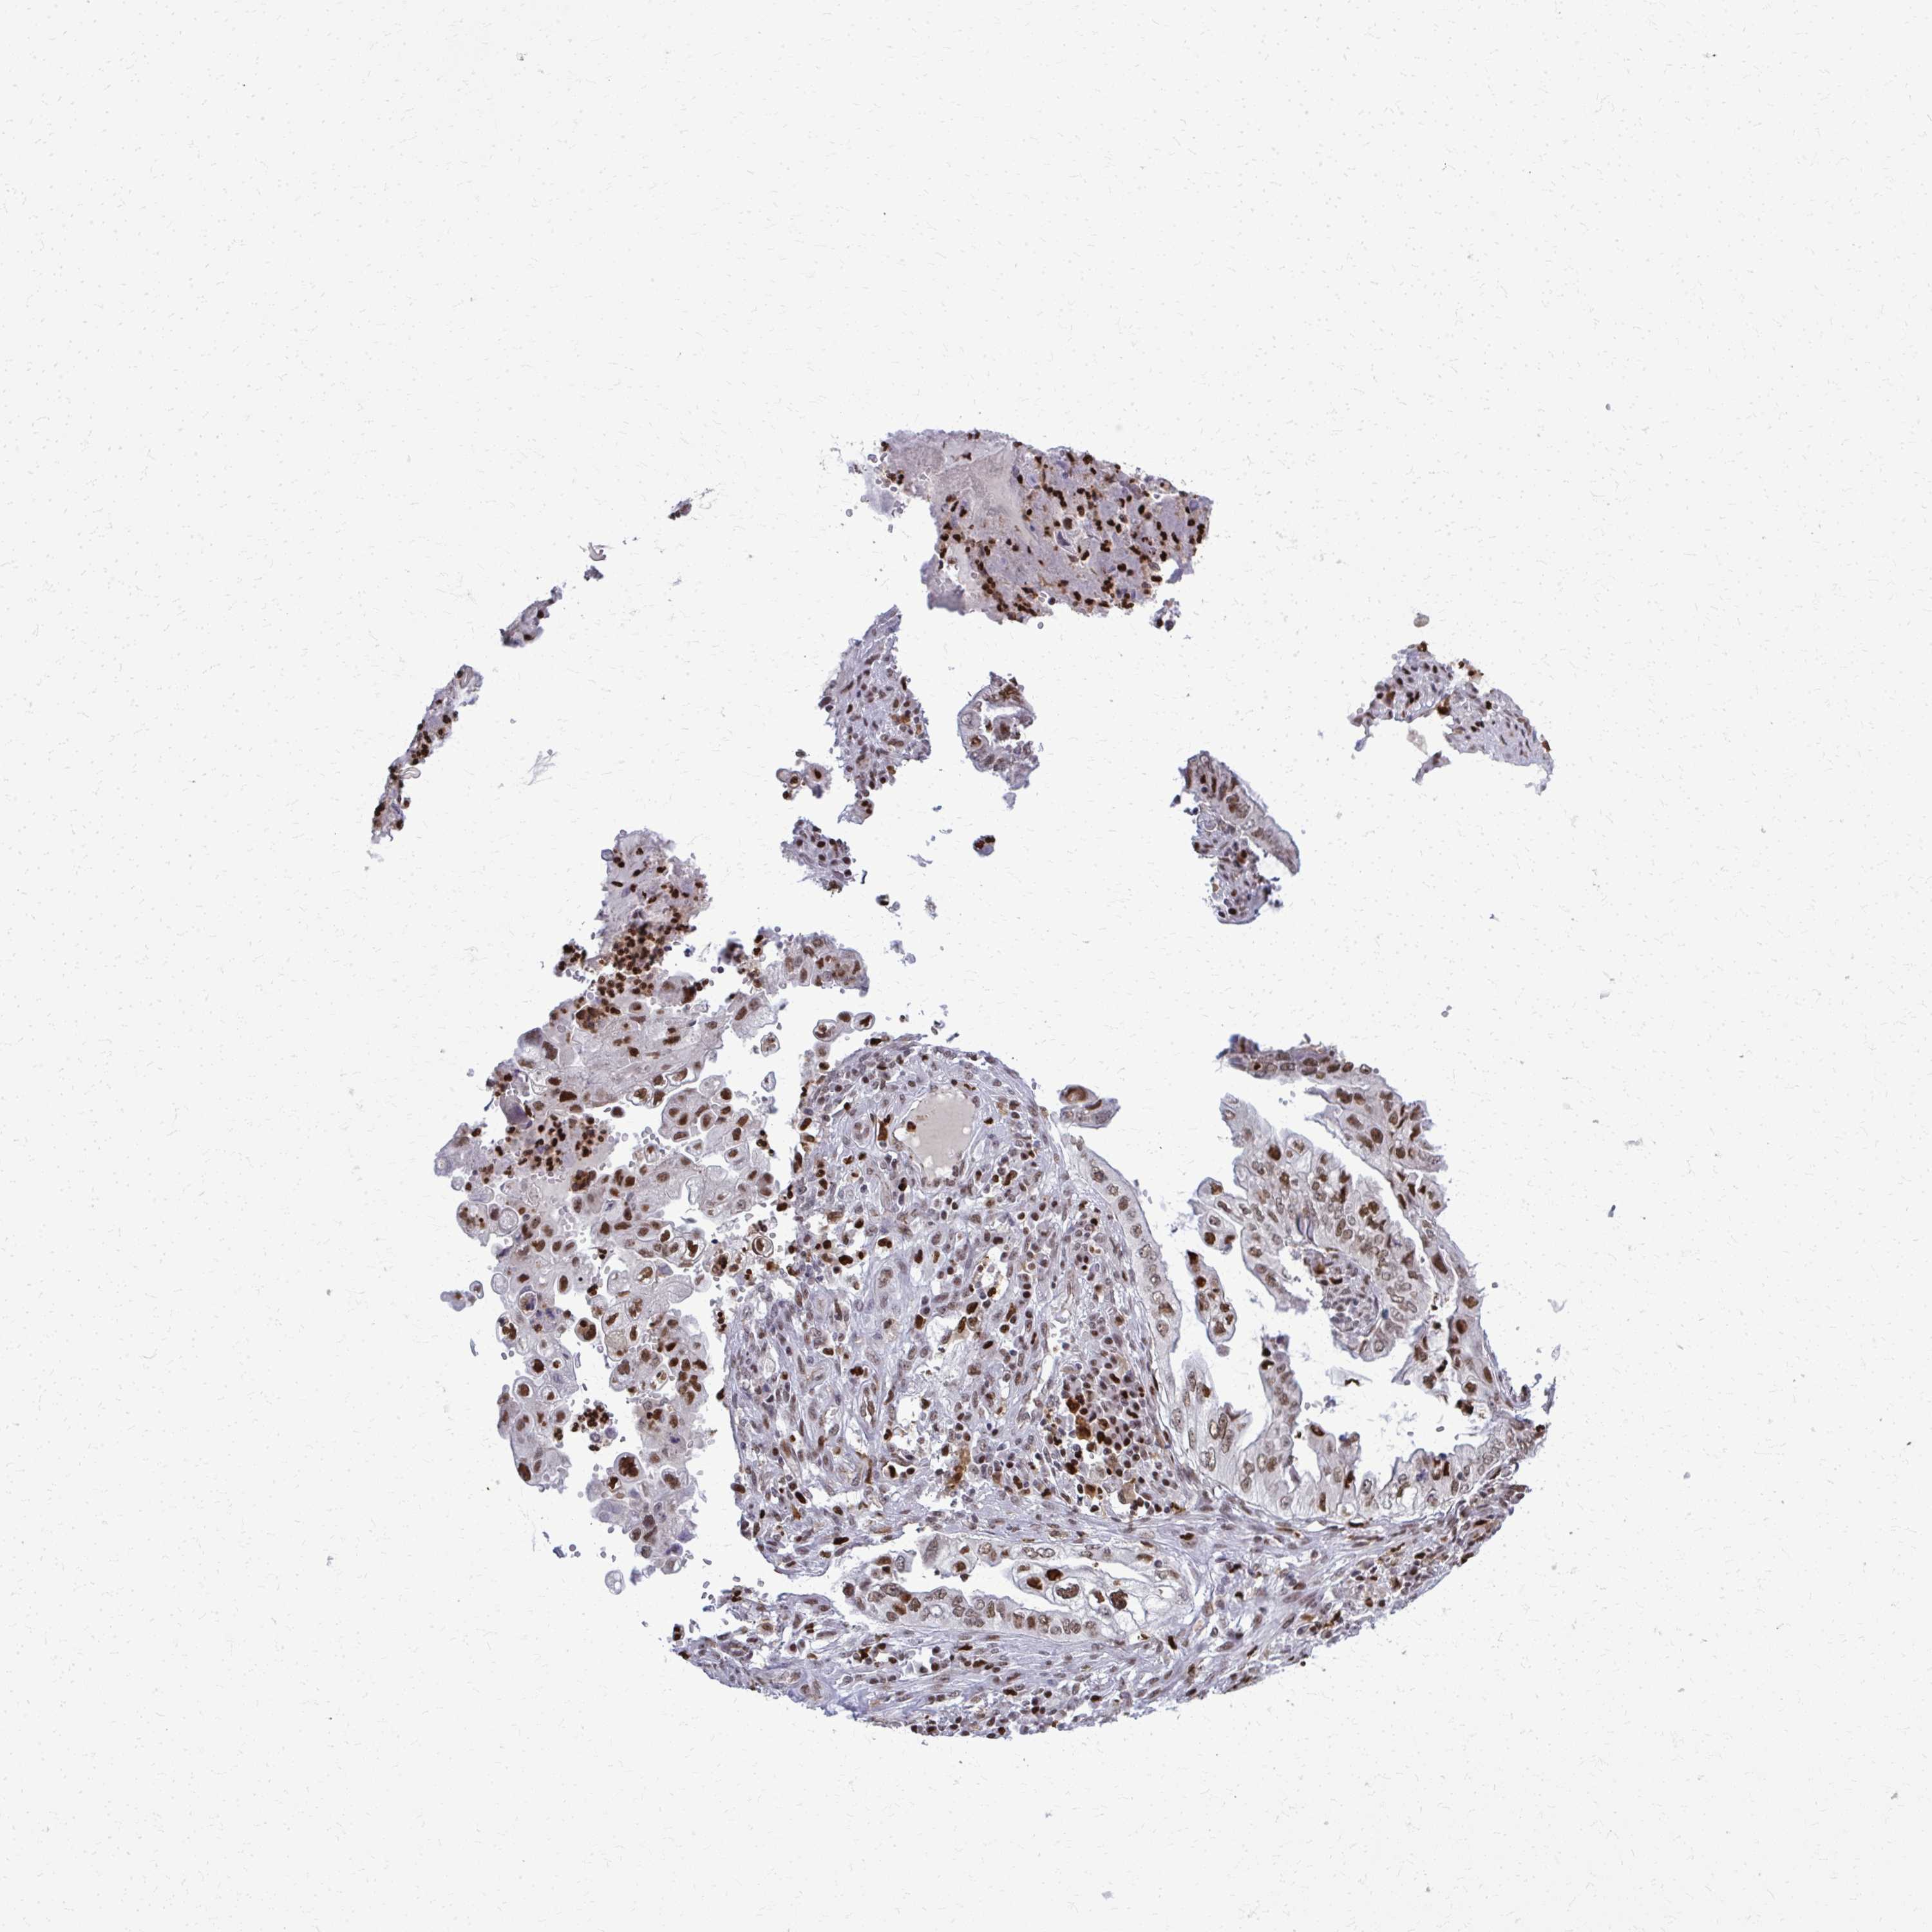

OVARIAN CANCER - Protein expressioni

A mouse-over function shows sample information and annotation data. Click on an image to view it in a full screen mode. Samples can be filtered based on level of antibody staining by selecting one or several of the following categories: high, medium, low and not detected. The assay and annotation is described here.

Note that samples used for immunohistochemistry by the Human Protein Atlas do not correspond to samples in the TCGA dataset.

Antibody stainingi

Antibody staining in the annotated cell types in the current human tissue is reported as not detected, low, medium, or high, based on conventional immunohistochemistry profiling in selected tissues. This score is based on the combination of the staining intensity and fraction of stained cells.

Each image is clickable and will lead to virtual microscopy that enables deeper exploration of all samples and also displays staining intensity scores, fraction scores and subcellular localization as well as patient and tissue information for each sample.

Antibody HPA059632

Staining

High

Medium

Low

Not detected

Intensity

Strong

Moderate

Weak

Negative

Quantity

>75%

75%-25%

<25%

None

Location

Nuclear

Cytoplasmic/membranous

Cytoplasmic/membranous,nuclear

Cystadenocarcinoma, serous, NOS

Carcinoma, NOS

Cystadenocarcinoma, mucinous, NOS

Carcinoma, endometroid